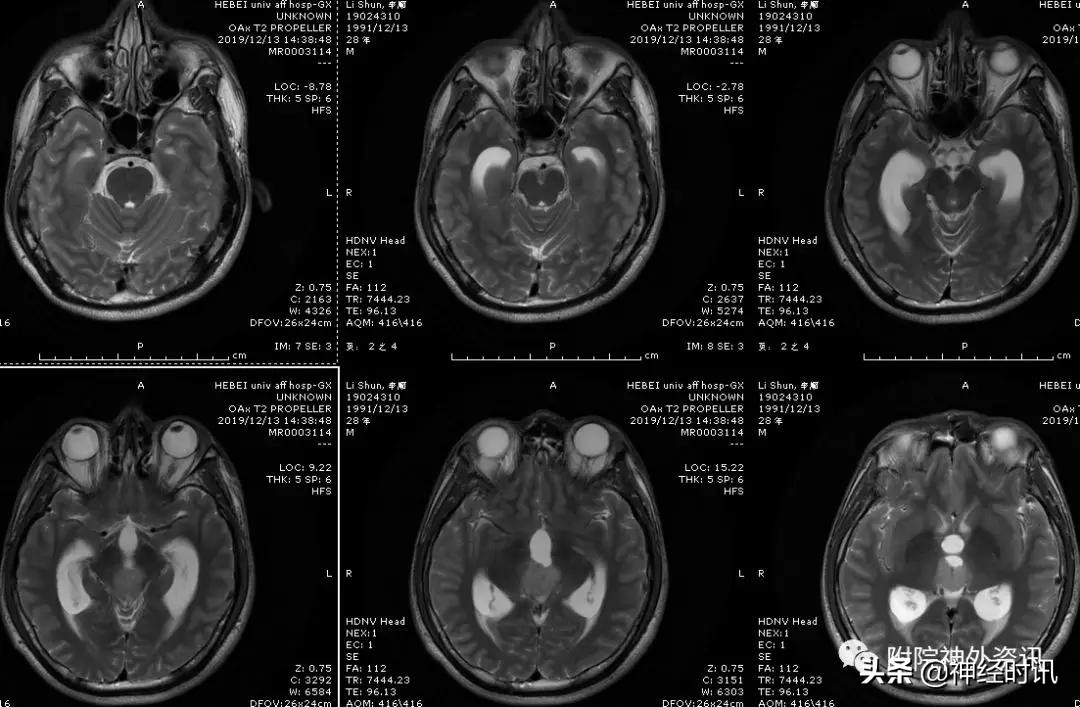

松果体区肿瘤影像表现各式各样,部分影像特征能鉴别出一些肿瘤性质。高分辨率的MRI能鉴别出肿瘤是来源于松果体还是附属结构。

生殖细胞瘤强化明显,边界清楚,沿着第三脑室侧壁生长,形成所谓的“蝶形征”。

畸胎瘤MRI信号高度非均一性,有较多密集的钙化和囊变,尤其是多样性的囊变,在T1WI和T2W均有较突出的高信号呈典型的“蜂窝状”改变。

男性,28岁,主因复视20余天入院,查体双瞳孔不等大,直径左=3. 5mm,右=3.0 mm,对光反射迟钝,双眼上视困难,左眼眼位异常,向内下斜视。